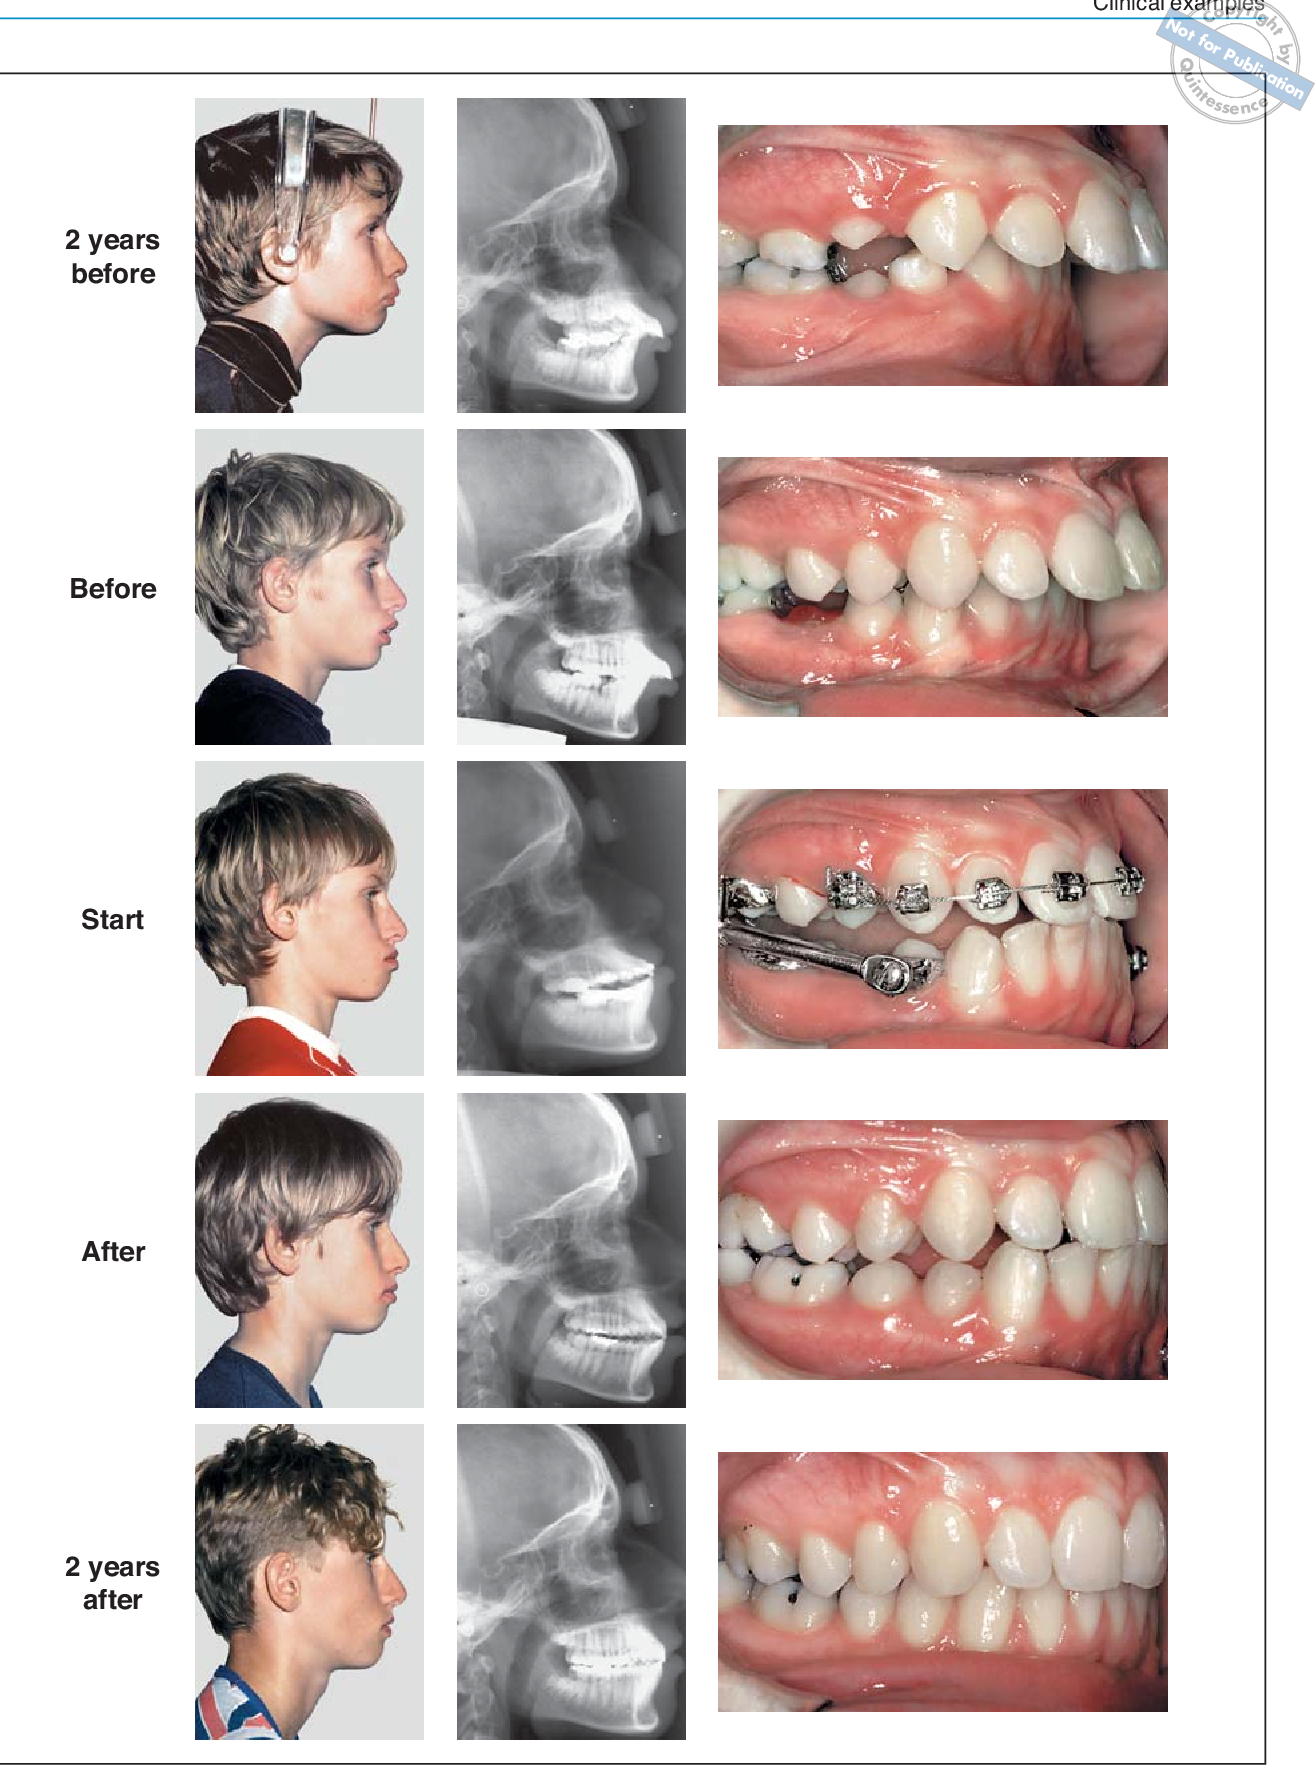

i said i dont know what his problem is since its only front profile but you can kinda tell his lower jaw is recessed. herbst fixes that. as for other orthodontic interventions just ask gpt its all common knowledgeyou just did by replying to it retard. Tell me what they can do to fix his skeletal jaw

wow 20-30% increase and still lookingthx for proving my point

nigga he's a duck in the first and second photoswow 20-30% increase and still looking

View attachment 4320264

"herbst fixes that" JFL

DENTAL INCLINATION HOLY SHIT BRO HIS LIPS CHANGED THAT'S ALL FUCK MAN IM GONNAnigga he's a duck in the first and second photos

View attachment 4320271